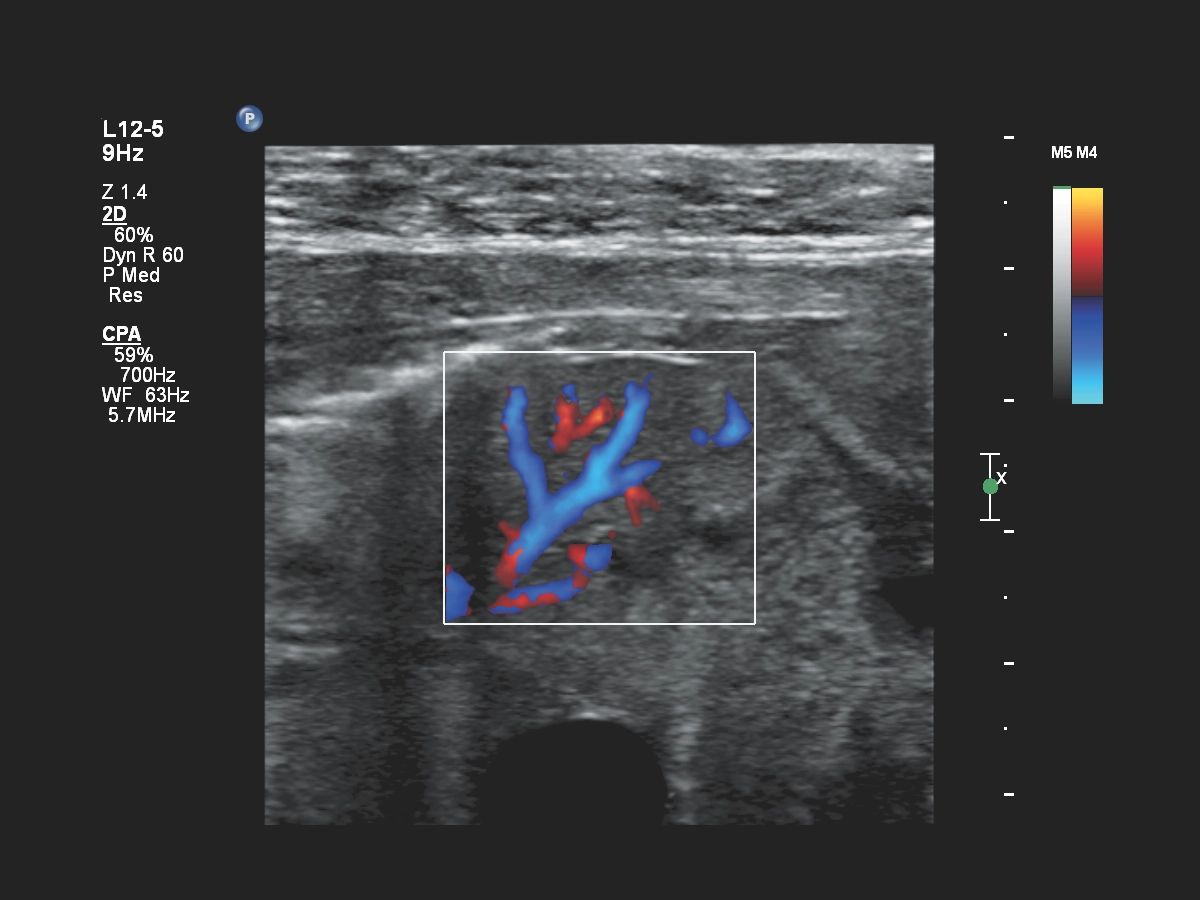

- Кардиология

Функции для кардио-исследований

- Stress Protokol - стресс эхокардиография

- GI 3DQ - количественный анализ 3D

- TDI - тканевый допплер

- Strain Q - функция для оценки скорости движения стенок миокарда

- A2DQ - автоматическое распознавание границ камер сердца и расчет площади, объема левого желудочка и параметров систолы и диастолы левого желудочка, расчет фракционной площади, фракции выброса, максимальной скорости выброса, максимальной скорости быстрого наполнения и фракции предсердного наполнения

- aCMQ - Анализ параметров общей и конкретной сократимости камер сердца

- MVI - функция для точной визуализации микрососудов при помощи картирования прохождения контраста по сосудам

- Contrast Card - функция для отображения микропузырьков в миокарде при введении контраста для анализа микроциркуляции в ЛЖ

- CMQ Stress - стресс эхокардиография для оценки глобальной и регионарной сердечной функции в различных состояниях